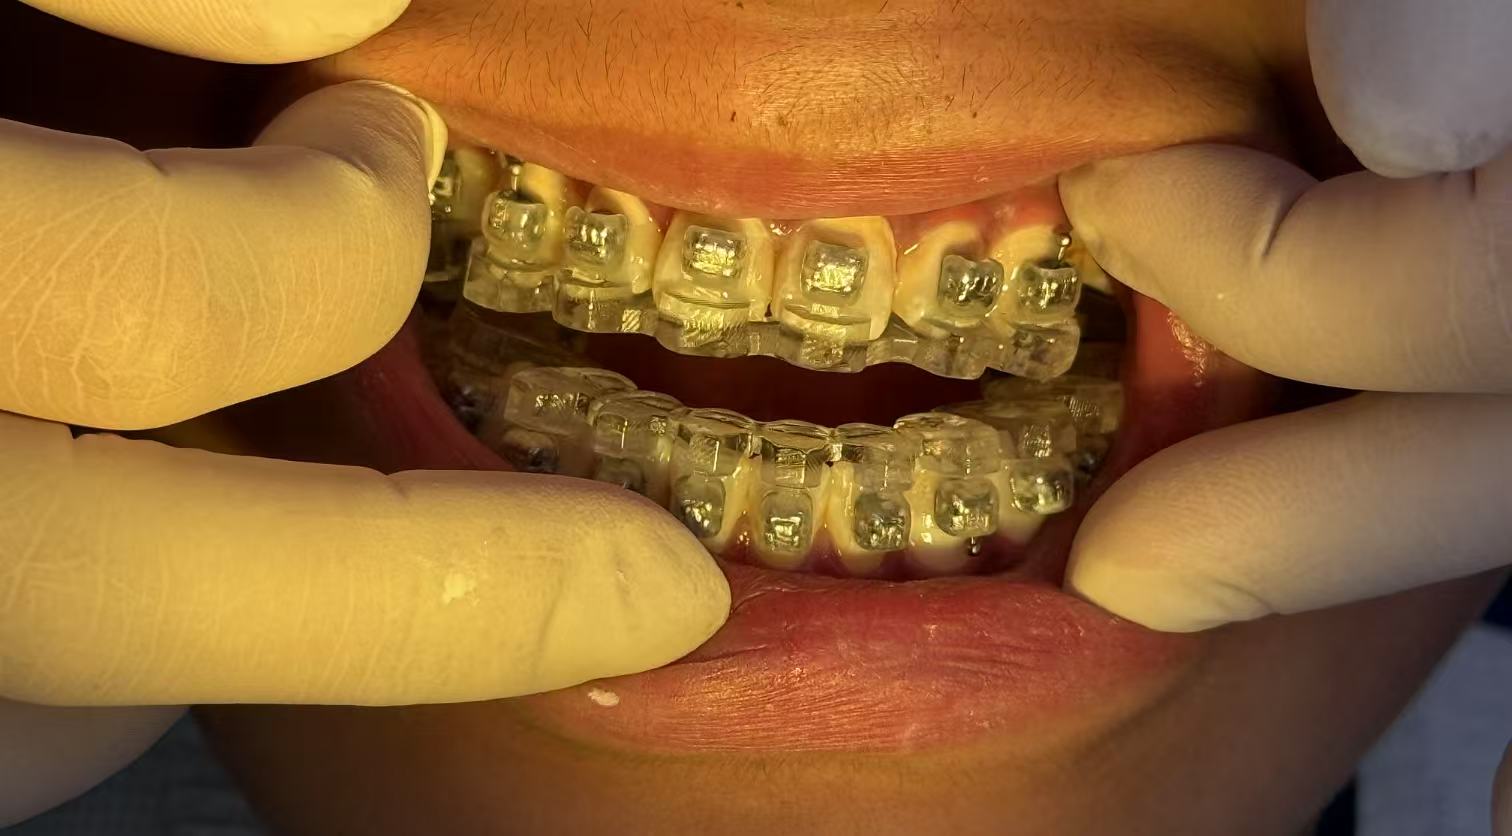

真实案例

TRUE CASE